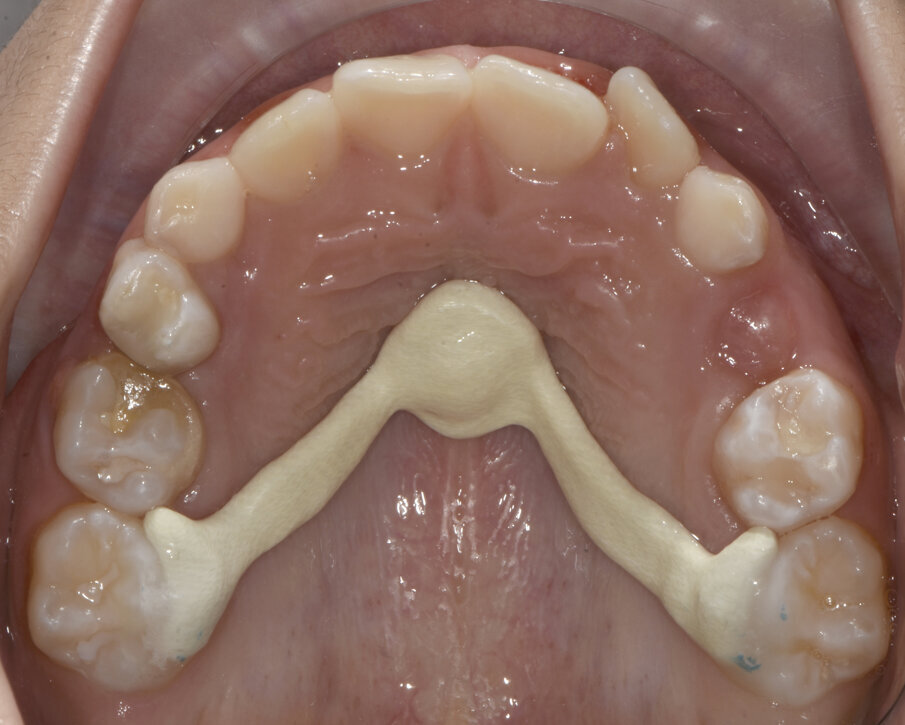

Dopo aver rilevato delle impronte con polivinilsilossano per realizzare un espansore del palato, si esegue l’espansione rapida del mascellare (Figg. 5, 6) superiore con il dispositivo cementato sui secondi molari decidui (5.5-6.5). Al termine dell’espansione, sono rilevate delle nuove impronte con polivinilsilossano per realizzare una barra palatale (Fig. 6) ancorata sui primi molari permanenti (1.6-2.6); viene eseguito un protocollo di estrazioni anticipate dei primi molari decidui e dei canini decidui (Figg. 7-9).

Fig. 7_Barra palatale, exo “D” ed eruzione 1.4-2.4.

Fig. 8_Ortopantomografia, correzione del percorso eruttivo di 1.3-2.3.

Al termine dell’espansione calibrata del mascellare superiore (Fig. 15), vengono presi dei nuovi modelli virtuali con i quali si realizza una barra di Nance (Figg. 16, 17) customizzata in Trilor® (Bioloren, Seregno, Italia). Il Trilor è una resina rinforzata con fibre, ha la caratteristica di essere molto leggera ed ha una rigidità ottimale; ciò consente il suo impiego in sostituzione del metallo per la fabbricazione di diversi device ortodontici.